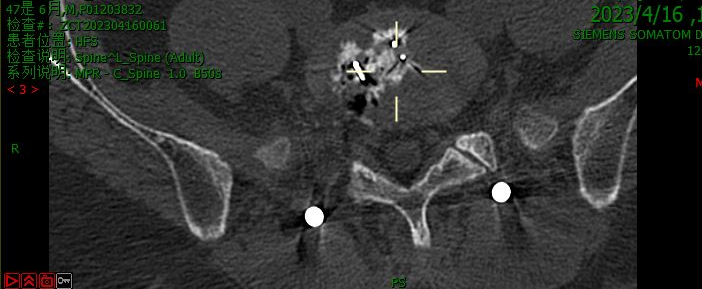

术前CT